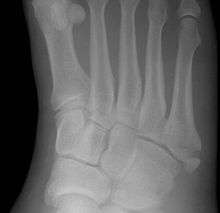

Other proximal fifth metatarsal fractures

Other proximal fifth metatarsal fractures exist, although they are not as severe as a Jones fracture. If the fracture enters the intermetatarsal joint, it is a Jones fracture. If, however, it enters the tarsometatarsal joint, then it is an avulsion fracture caused by pull from the peroneus brevis. An avulsion fracture is sometimes called a Pseudo-Jones fracture or a Dancer's fracture.